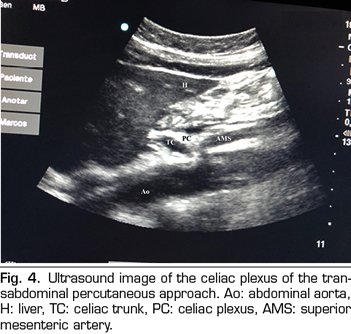

PERCUTANEOUS ULTRASOUND-GUIDED CELIAC PLEXUS NEUROLYSIS

In recent years, ultrasound has made head against fluoroscopy and CT in interventional pain management. The first describing the technique on the celiac plexus was Bhatnagar (31), and it could be performed percutaneously at the patient’s bedside and supine, which gives greater comfort for both the patient and the doctor. However, there are still no randomized controlled trials comparing abdominal ultrasound neurolysis of the celiac plexus versus opioid systemic treatment. The technique is performed using a convex transducer (2-5 MHz), initially placed just below the xiphoid process in the transverse plane, to identify structures, such as liver, stomach, intestine, portal veins, cava and aorta. With the help of the Doppler, we scanned caudally to identify the bifurcation of the celiac trunk in the hepatic and splenic arteries, and more distally in the superior mesenteric artery. Then we rotate the transducer in the longitudinal plane, visualizing in the same image the bifurcation of the aorta in the celiac trunk and in the superior mesenteric artery with the celiac plexus surrounding these structures. The approach is performed in plane, transabdominal, through the liver or stomach, as long as there are no large vessels interfering with the needle path (Figure 4).